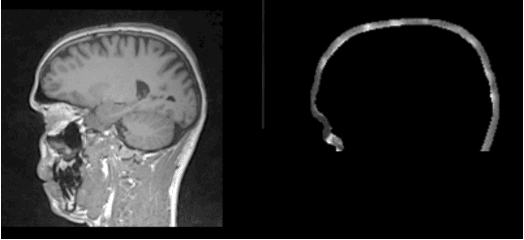

Abstract:Simultaneous EEG/fMRI acquisition allows to measure brain activity at high spatial-temporal resolution. The localisation of EEG sources depends on several parameters including the position of the electrodes on the scalp. The position of the MR electrodes during its acquisitions is obtained with the use of the UTE sequence allowing their visualisation. The retrieval of the electrodes consists in obtaining the volume where the electrodes are located by applying a sphere detection algorithm. We detect around 90% of electrodes for each subject, and our UTE-based electrode detection showed an average position error of 3.7mm for all subjects.